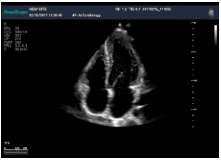

(4)轉(zhuǎn):整個超聲探頭平面緊貼受檢區(qū)域皮膚,以超聲探頭與胸壁的接觸點為支點,超聲探頭以自身中軸線順時針或逆時針方向旋轉(zhuǎn)一定角度。

四腔心